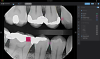

Fig 1. A bitewing radiograph displayed with clinical AI detections and bone level measurements. Caries detections (fuchsia) indicate depth of decay into various tooth structures. Calculus (green) and a notable margin (purple) are also highlighted in this example.

Figure 1